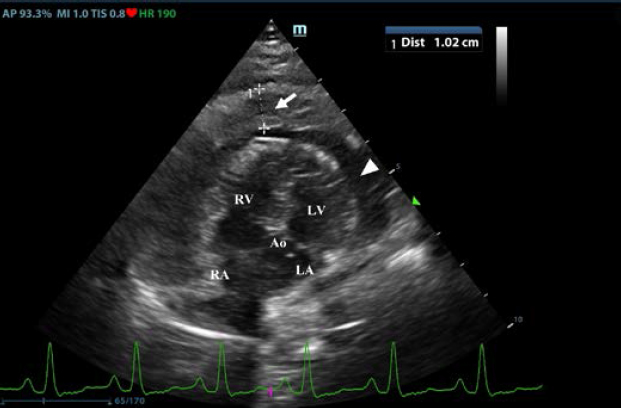

Fig. 1. Transthoracic echocardiogram – right parasternal long-axis four-chambered view. Note the pericardial effusion, the right atrial collapse (white arrow), the thickened, hyperechoic pericardium, and the scant pericardial effusion (white arrowhead). LA: left atrium; LV: left ventricle; RA: right atrium; and RV: right ventricle.

First, transthoracic echocardiogram findings were a small amount of circumferential tamponating pericardial effusion (Fig. 1) and a severe hyperechoic pericardial thickening (10.2 mm) (Fig. 2). The right atrium was normal in size and there was collapse during systole. There was mild septal flattening seen on short axis view of the left ventricle. A short-axis left ventricular M-mode showed posterior displacement of the interventricular septum during late diastole at the time of atrial systole (Fig. 3). The epicardium and pericardium had a hyperechoic appearance with a thin, shaggy layer of heterogeneous echogenic material lining the surface of each (Fig. 1, Supplementary Video I). Pericardiocentesis was not recommended at this time given that the patient was minimally clinically and hemodynamically affected. Few hours later, a second echocardiographic examination, after stabilization of left ventricular volume with intravenous (IV) lactate ringer solution at maintenance rate, showed a worsening of pericardial thickness (13 mm) and an increase in pleural effusion. Furthermore, there was a >25% mitral inflow variation noted with respiration. In addition, there was >30% tricuspid inflow variation with respiration, signs of CP. During the second echocardiography, the patient appeared to be slightly dyspneic due to the increased thoracic effusion.